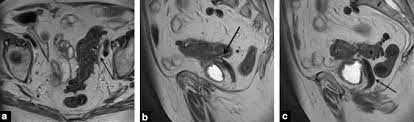

Digestive Diseases Mimicking Primary Gynecological Diseases Or With Secondary Gynecological Manifestations Sciencedirect from ars.els-cdn.com Can ovarian cancer be found early? Guide to causes, symptoms, survival rates, ovarian cancer treatment options, fertility problems, prevention guidelines. Memorial sloan kettering experts discuss ovarian and breast cancer prevention and treatment in women with a brca mutation. Ovarian cancer, or cancer of the ovaries, is one of the most common types of cancer in women. At this time, based on available studies, having a history of cancer may increase your risk. Ovarian cancers are a group of diseases that affect the ovaries. The best course of treatment and the prognosis depend on the stage, type, and grade of the cancer. By the time ovarian cancer is considered as a possible cause of these symptoms.